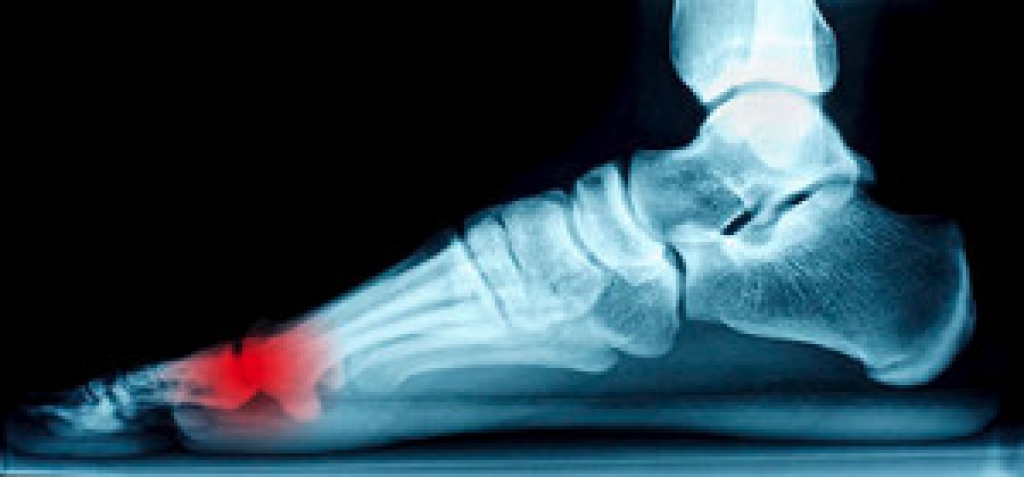

The Achilles tendon is a tough band of tissue that connects the calf muscles to the heel bone. An Achilles tendon rupture is an injury in which this tendon tears. This often happens during a sudden, forceful movement of the foot downward against resistance, for example, when an athlete pushes off the foot forcefully to jump. The symptoms of an Achilles tendon rupture is a sudden, sharp snap and intense pain in the back of the leg, an inability to point the foot downward, and difficulty walking. Swelling may also occur. If you suspect that you have ruptured your Achilles tendon, it is suggested that you seek the care of a podiatrist.

The Achilles tendon is a tendon that connects the lower leg muscles and calf to the heel of the foot. It is the strongest tendon in the human body and is essential for making movement possible. Because this tendon is such an integral part of the body, any injuries to it can create immense difficulties and should immediately be presented to a doctor.

- Extreme pain and swelling in the foot

Achilles tendon injuries are diagnosed by a thorough physical evaluation, which can include an MRI. Treatment involves rest, physical therapy, and in some cases, surgery. However, various preventative measures can be taken to avoid these injuries, such as: